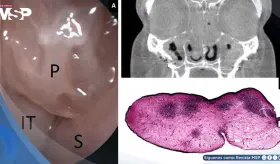

La cirugía reveló tres testículos izquierdos independientes, sin presencia de cáncer, y el paciente logró alivio total del dolor tras la orquiectomía y colocación de una prótesis.